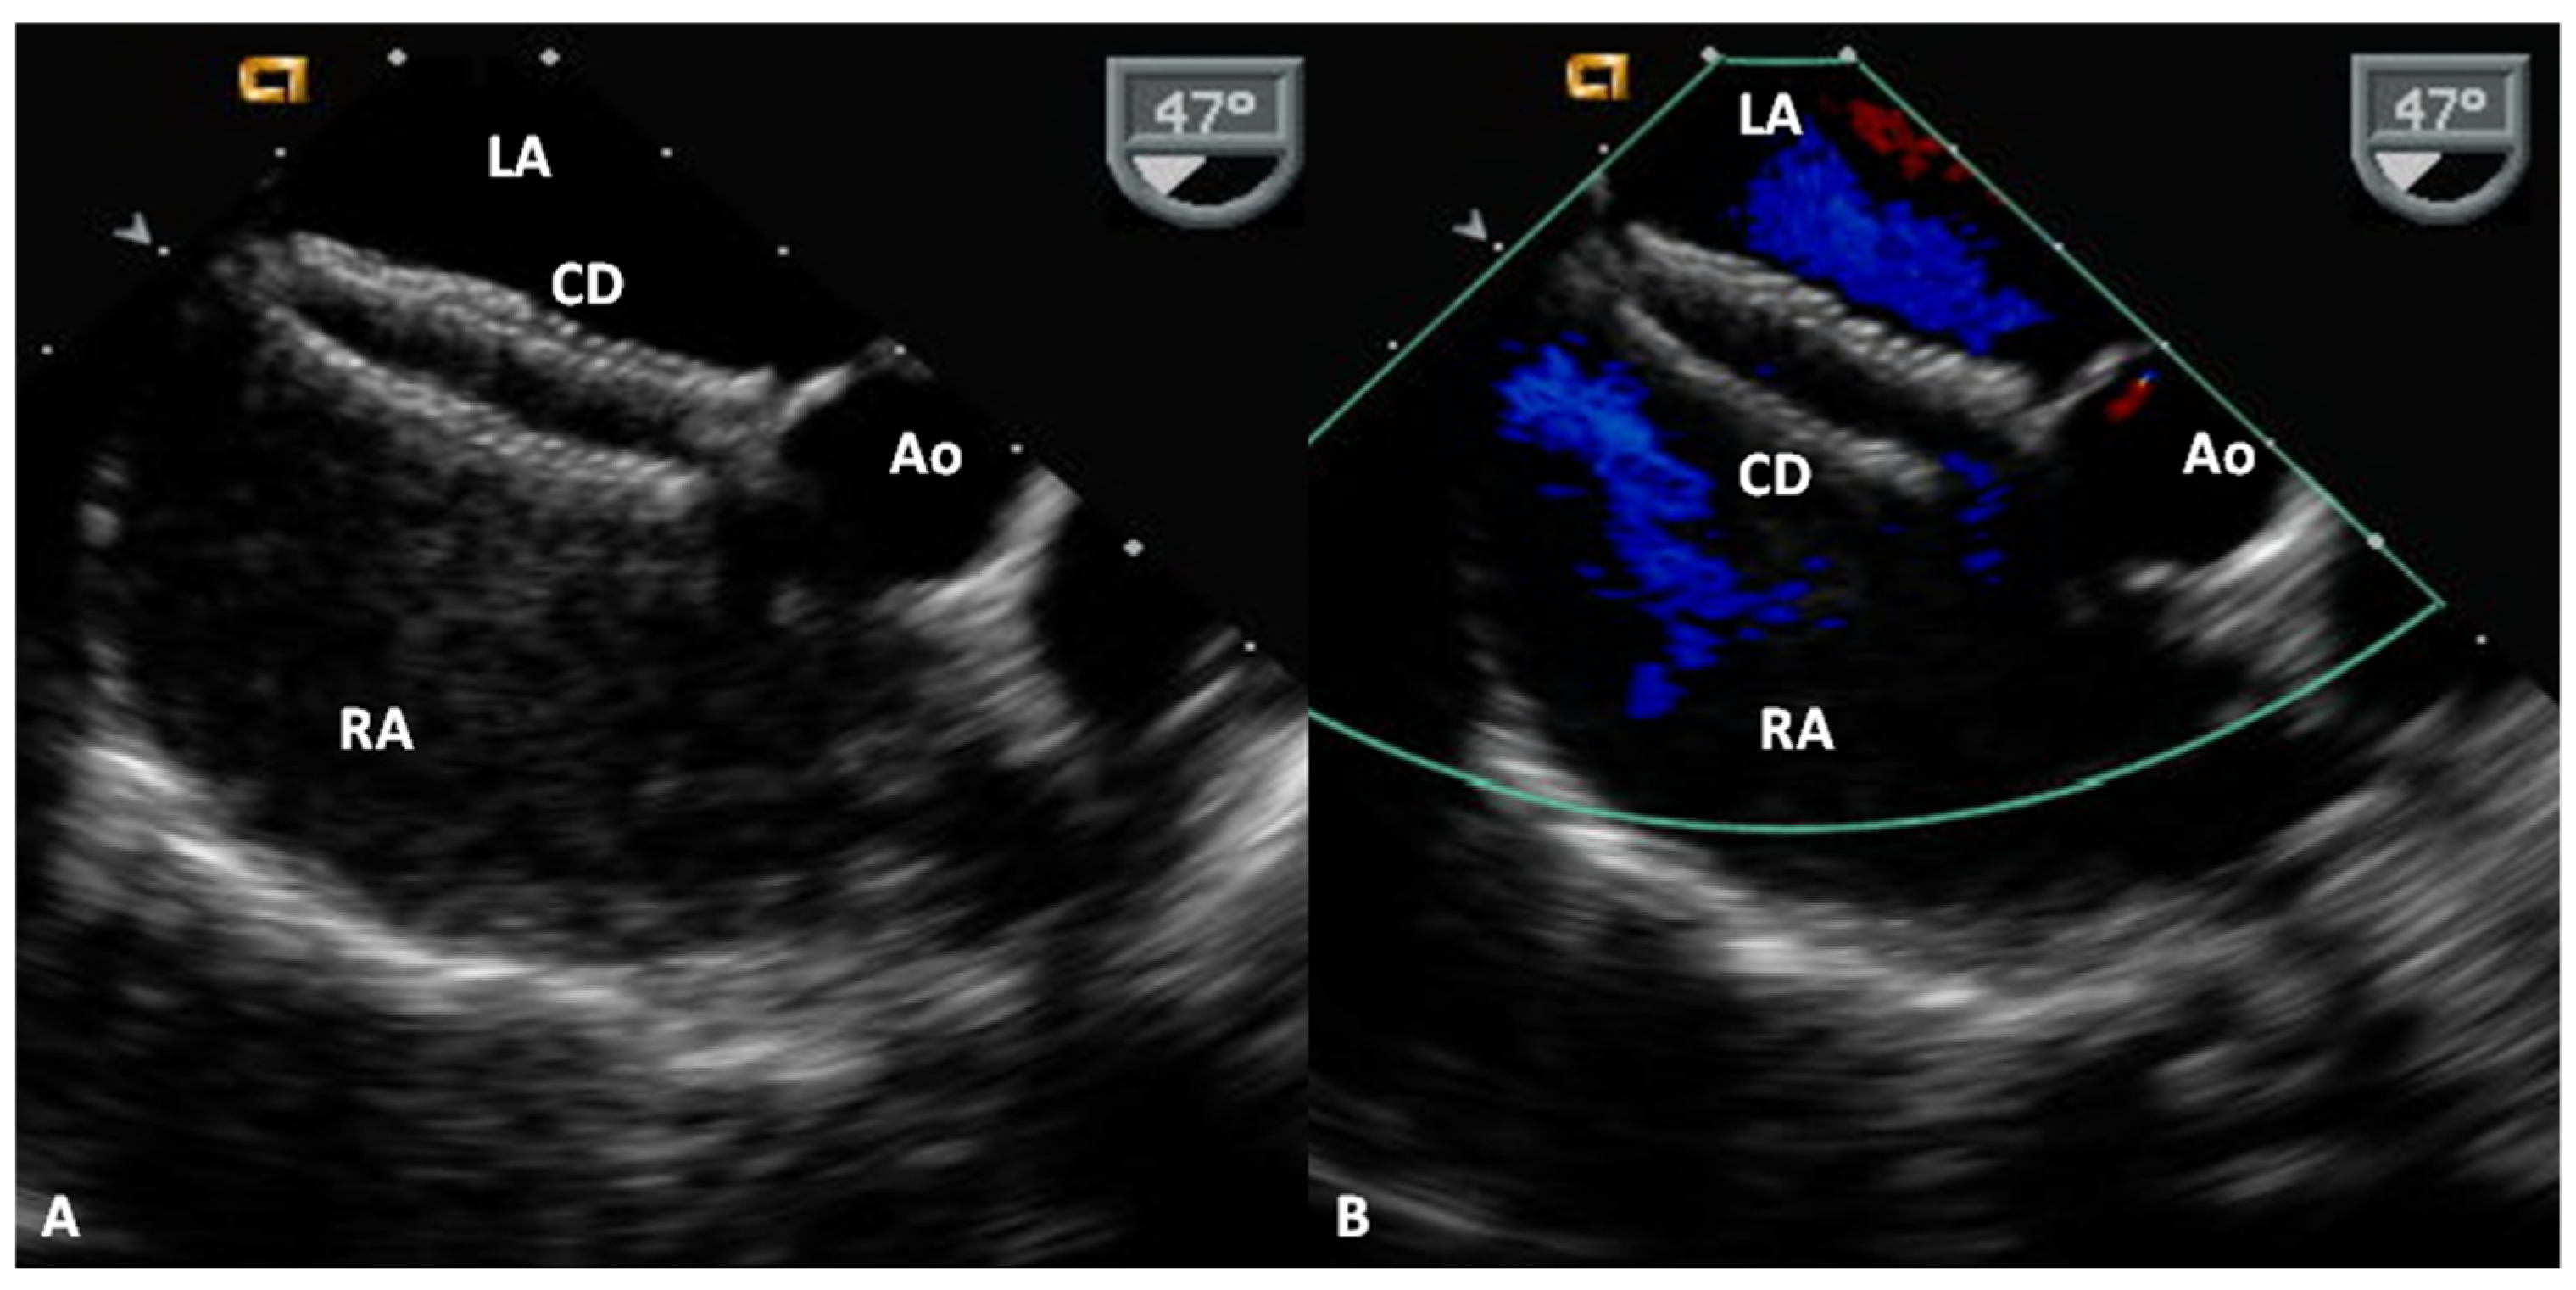

- Tsai, S.K.; Hsiung, M.C.; Wei, J.; Lee, Y.-T.; Yu, H.-P.; Ou, C.-H.; Yin, W.-H. Transesophageal echocardiography for incremental value of Amplatzer cribriform septal occluder for percutaneous transcatheter closure of complex septal defects: Case series. J. Chin. Med. Assoc. 2017, 80, 333–340. [Google Scholar] [CrossRef] [PubMed]